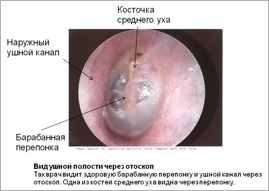

Осмотр ушной полости

Во время обследования ваш врач может использовать специальное приспособление для осмотра ушной полости называемое отоскопом, который позволяет заглянуть внутрь уха и исследовать ушной канал и барабанную перепонку.

Для изучения естественных отверстий организма, таких, например, как ушной канал, врачу обычно нужен источник света, который можно сфокусировать на осматриваемом участке. Кроме того, необходимо устройство, позволяющее увеличивать изображения. Эти два компонента (источник света и увеличитель) часто объединяются в один инструмент, такой как отоскоп, который используется для изучения ушного канала.